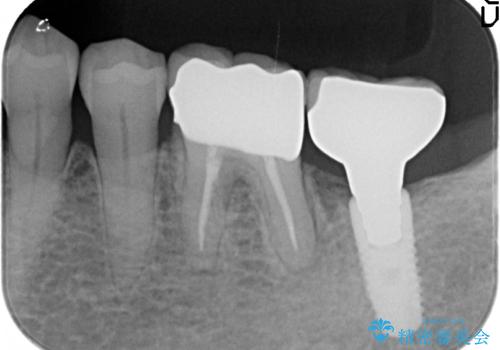

検査の結果、左下6番目の歯は神経が死んでおり根尖に病変が出来ていたため、根管治療を行いました。

その後症状の消失を確認後、オールセラミッククラウンによる補綴を行いました。

今回用いたオールセラミッククラウンはジルコニアフレームという白い素材の上にセラミックを盛っているため、審美性が非常に高いのが特徴です。

また、ジルコニアは人工ダイヤモンドの材料にも使われているほど高い強度を持っており、そのためオールセラミッククラウンは審美性だけでなく、奥歯やブリッジの補綴も可能とするクラウンです。